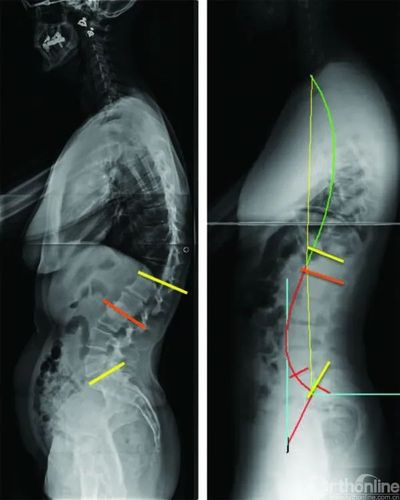

4改变顶点位置_从4种腰椎前凸临界点探寻腰椎退变过程

在正常情况下 脊柱有4个弯曲 —— 颈椎前凸,胸椎后凸 腰椎前凸和骶

正常的腰椎是有生理前凸的,而很多腰椎病患者由于长期姿势不良,外伤